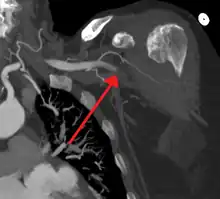

Acute occlusion of the axillary artery resulting in an ischemic limb as seen on CT angiography

In order to treat acute limb ischaemia there are a series of things that can be done to determine where the occlusion is located, the severity, and what the cause was. To find out where the occlusion is located one of the things that can be done is simply a pulse examination to see where the heart rate can be detected and where it stops being sensed. Also there is a lower body temperature below the occlusion as well as paleness. A Doppler evaluation is used to show the extent and severity of the ischaemia by showing flow in smaller arteries. Other diagnostical tools are duplex ultrasonography, computed tomography angiography (CTA), and magnetic resonance angiography (MRA). The CTA and MRA are used most often because the duplex ultrasonography although non-invasive is not precise in planning revascularization. CTA uses radiation and may not pick up on vessels for revascularization that are distal to the occlusion, but it is much quicker than MRA.[10] In treating acute limb ischaemia time is everything.